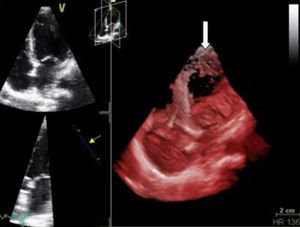

Monitorizada em ambiente de unidade de cuidados intensivos cardíacos, realizou ecocardiograma, que revelou ventrículo esquerdo de dimensões normais com fracção de ejecção do ventrículo esquerdo (FEVE) global ligeiramente deprimida (FEVE ± 45%) e imagens compatíveis com VENC a nível apical (trabeculações exuberantes com relação camada trabeculada/não trabeculada superior a dois e com fluxo detetado por Doppler de cor ao nível das mesmas) (Figuras 4 e 5). Foi efetuada coronariografia, revelando ausência de doença coronária.

A paciente teve alta clinicamente estável. Atualmente, encontra-se bem, sem sinais clínicos de ICC. Encontra-se dependente da função pacing do CDI de dupla câmara, sem choques detetados. O rastreio de familiares diretos revelou ECG normais, com os ecocardiogramas dos seus filhos a revelarem imagens sugestivas de não compactação miocárdica inferior e lateral (Figura 6) (com o ECG de alta resolução dos mesmos a não revelar alterações). Aguarda-se atualmente o estudo genético da paciente.